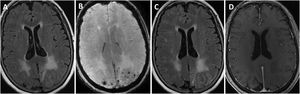

Hallazgos de RM craneal en la inflamación relacionada con Angiopatía amiloide (paciente 6).

Mujer de 83 años, con cuadro agudo de desorientación, confusión y crisis epiléptica. La resonancia magnética (RM) craneal muestra afectación de la sustancia blanca parietal bilateral, de predominio izquierdo (A). Asocia múltiples microhemorragias de distribución cortical en el margen posterior de ambos lóbulos parietales en susceptibilidad magnética (B) y captación leptomeníngea en el interior de los surcos que se identifica con mayor claridad en secuencias FLAIR (C) que en secuencias potenciadas en T1 con contraste (D).